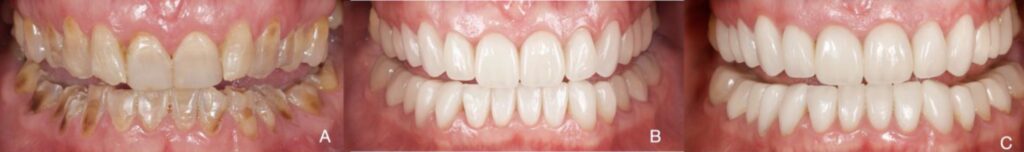

Figure 1. Patient 1. Generalized extreme pathological tooth wear (TWES 2.0). (A) Intraoral initial aspect

of one Sjogren’s syndrome diagnosed. Deep-bite occlusal relationships and severely worn anterior

teeth and severe tetracycline staining can be appreciated. (B) Intraoral aspect after orthodontic and

restorative treatment, emphasizing great aesthetic and functional improvement. Occlusal-vestibular

veneers from 1.6 to 2.6 and from 3.1 to 4.2. In the posteroinferior sectors (3.3–3.7 and 4.3–4.7), CAD-CAM

nanoceramic resins were used. (C) A 5-year follow-up photograph. Note the maintenance of occlusal

contact relationships, although there is slight wear of the posteroinferior sectors, as seen in the flattening

of the cusps. (D) Initial orthopantomography. (E) Final orthopantomography showing the supplement

of all teeth with an endodontic treatment in 4.5 due to previous necrosis.